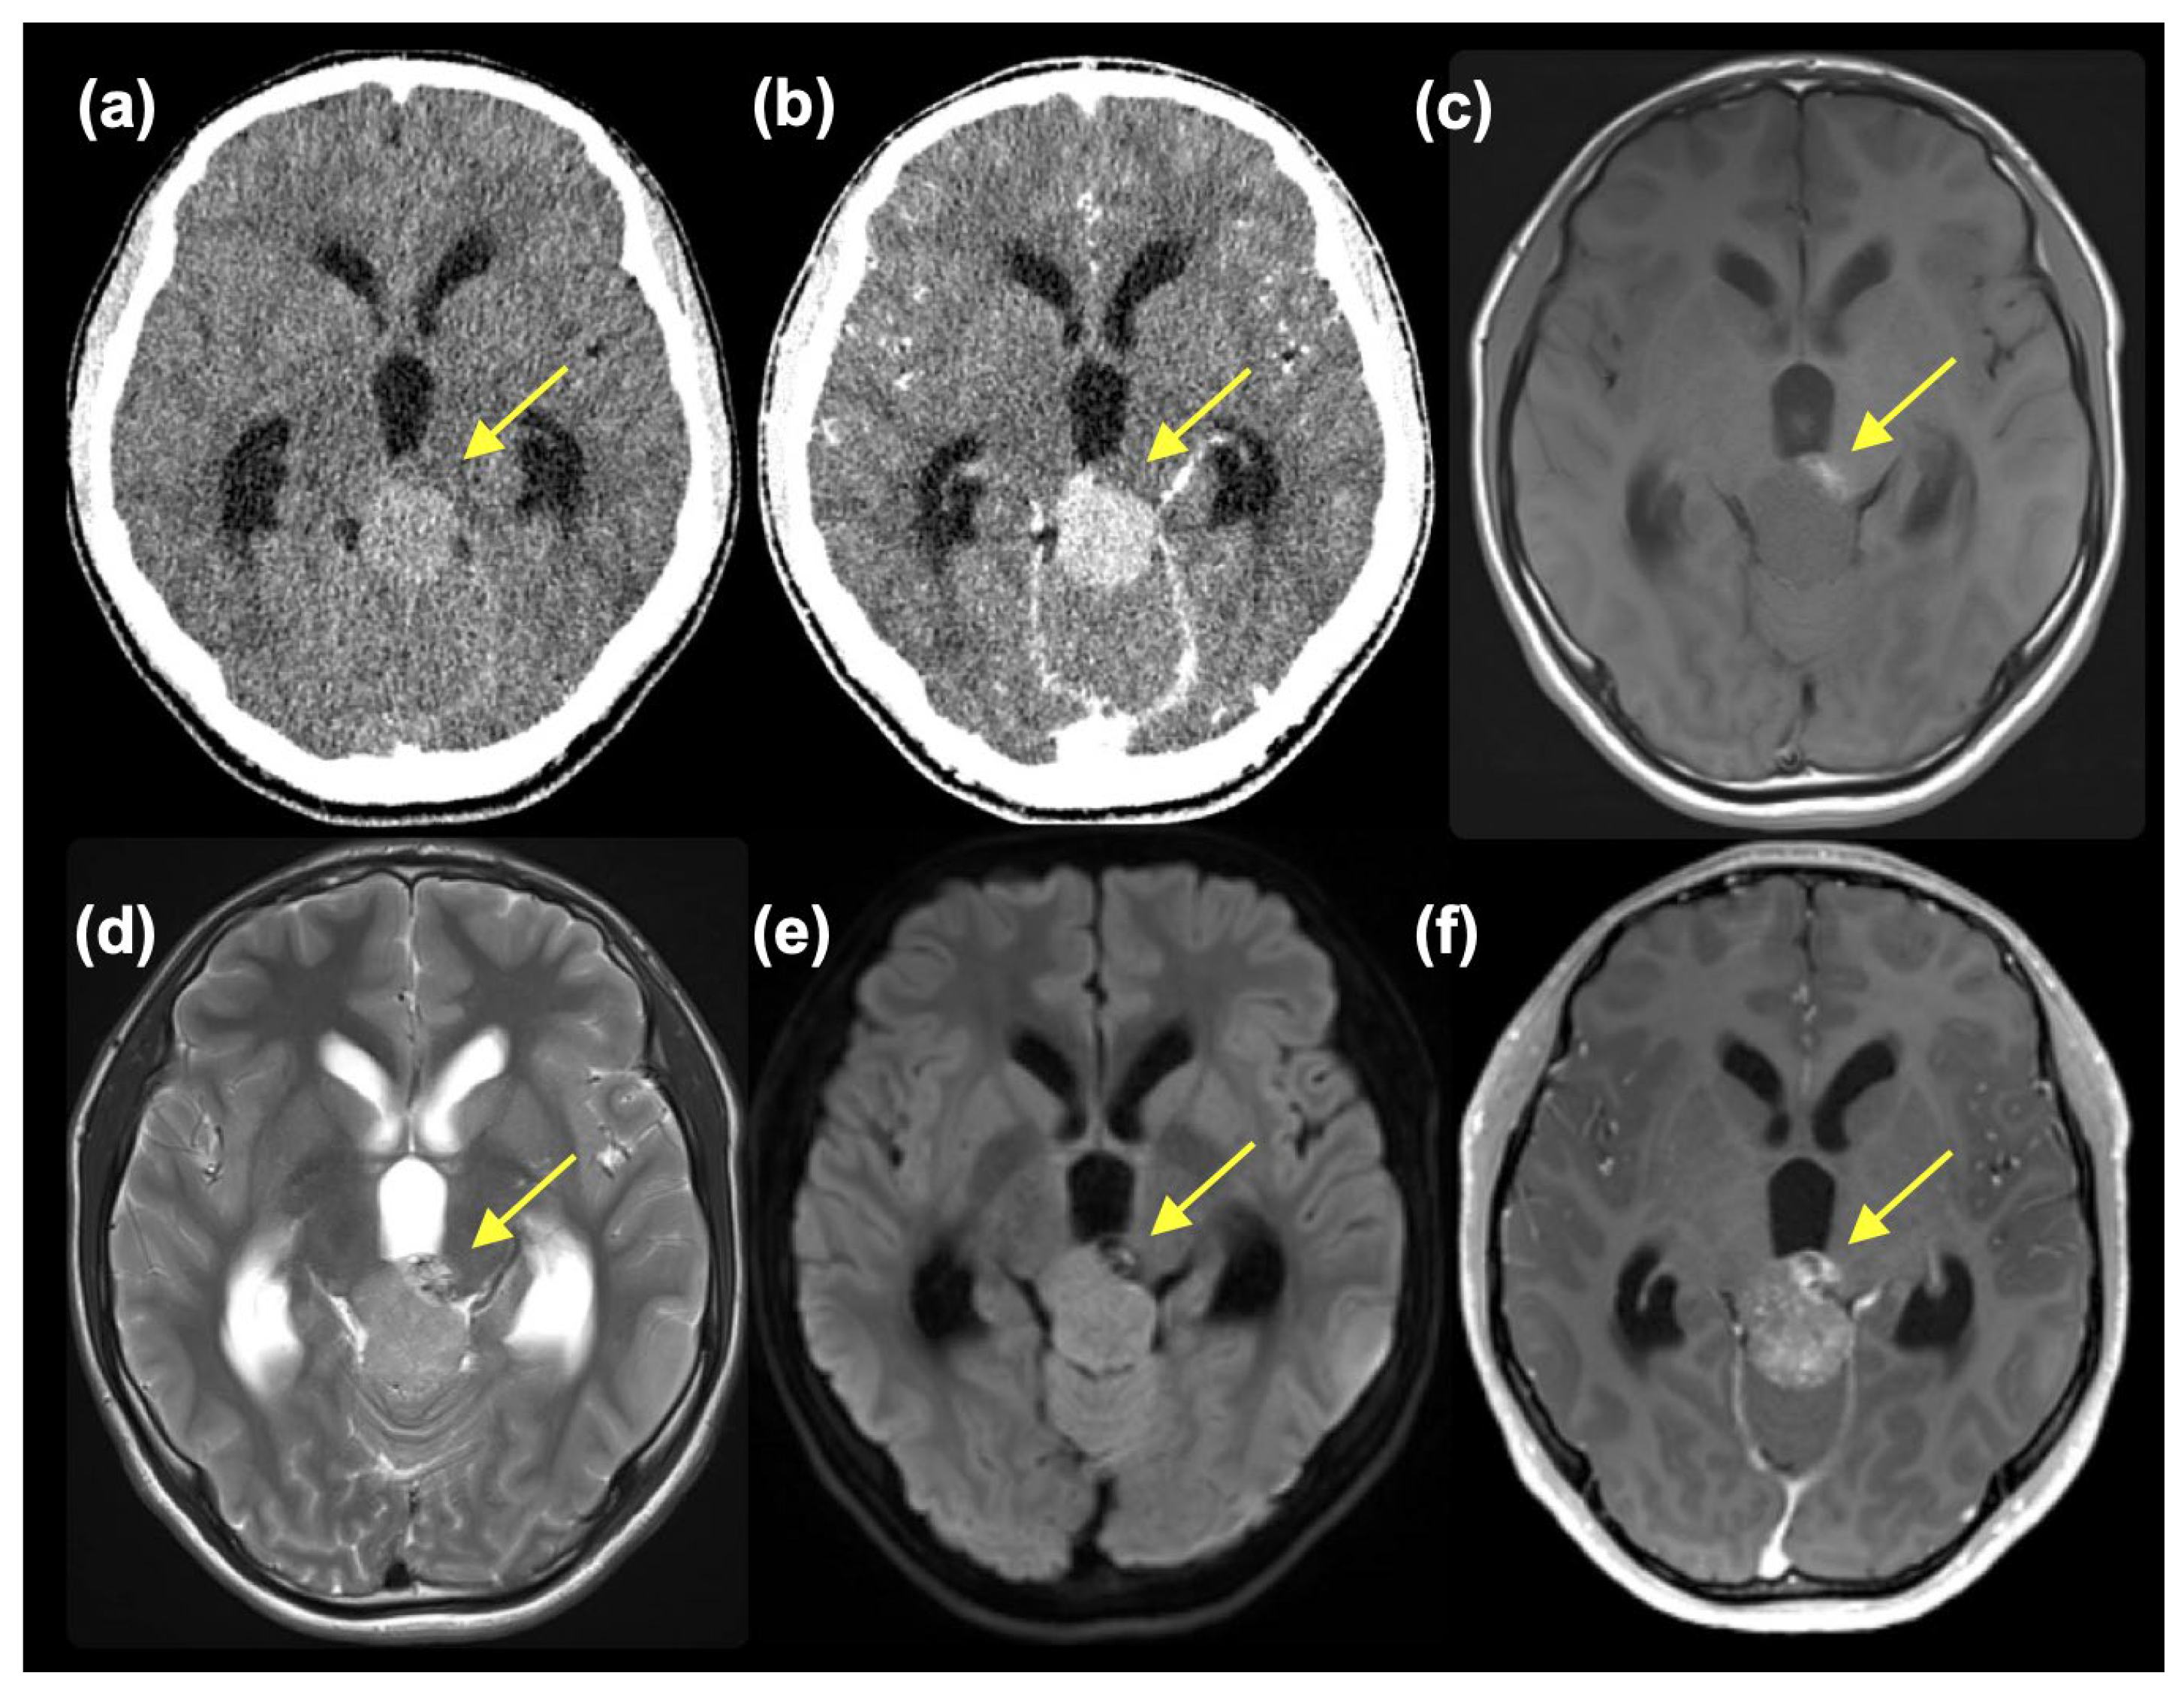

2. Case Presentation